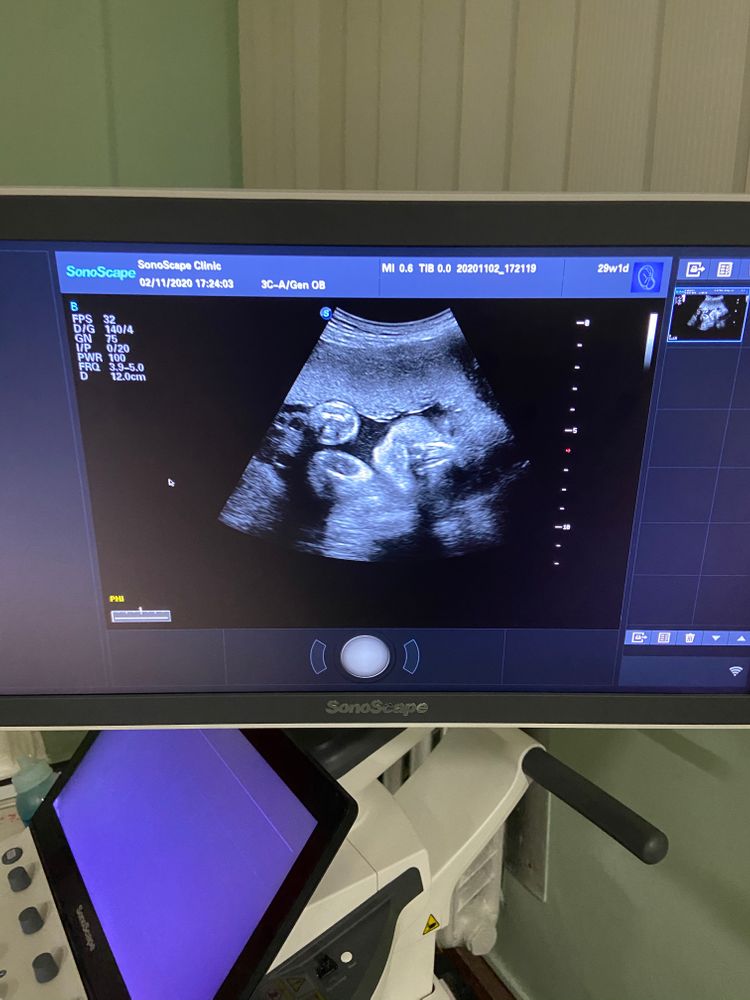

Фото УЗИ 30-31 недель

🥰Истинная леди умеет кокетничать и позировать с утробы. Вот. Уже боюсь её инстаграма😄

Доплер, ктг и прочие измерения прошли на ура. Девочка растёт по сроку, вес 1,6-1,8 кг, очень активная умничка, но имеется угроза преждевременных родов из-за укорочения шейки матки😞 очень не хочется рожать так рано!! Кто как справлялся с такими же диагнозами на этом сроке? Чем закончилось